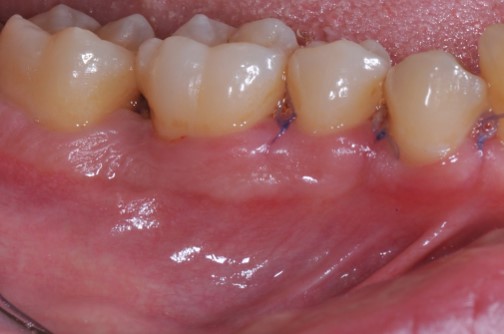

Radiographic view before periodontal regenerative therapy with Straumann® Emdogain®. A deep intrabony defect appeared mesially and distally on the left mandibular first premolar. Pre-surgical probing measured 8 mm. The defect morphology presented as well-contained.